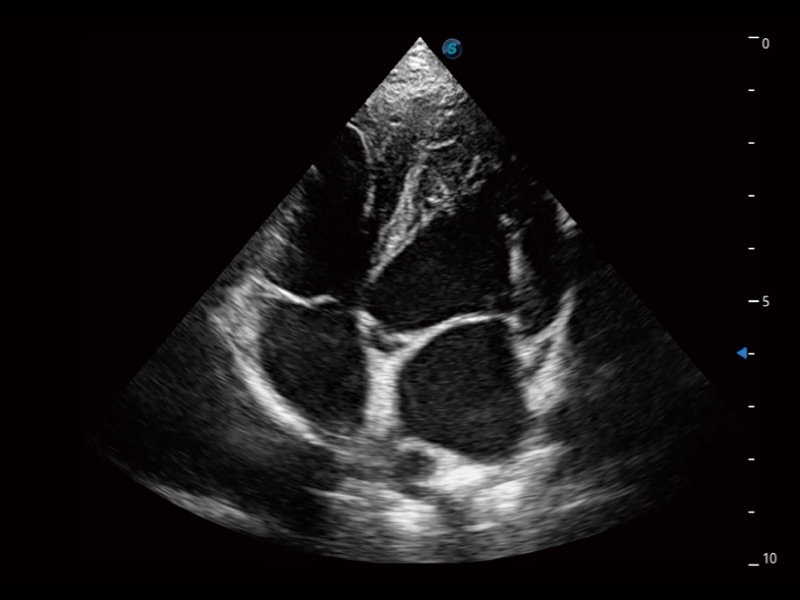

动物是人类最亲密的朋友和最值得信赖的伙伴。乐玩lewin国际也一直致力于探索动物专用的超声影像解决方案。全新推出的ProPet系列,是乐玩lewin国际在动物超声影像智能化、专业化、精准化的一次跨越式革新。动物不能用言语来表述自己的不适,通过超声影像,ProPet系列搭建了动物医生与不同物种沟通的“桥梁”,为动物医生注入了“治愈之力”。 ProPet 70将是您值得信赖的超声伙伴。它配备了复合材料线阵探头,帮助动物医生获得卓越精准的临床图像。同时ProPet 70直观便捷的操作体验以及专业的测量工具,可为不同体型和生理结构的动物带来全面临床评估,切实为动物医生提供智能、专业、精准的超声影像解决方案。

ProPet 70 进一步提升了微米成像算法,更加注重对基础原始图像的还原和保留,在有效减少斑点噪声、增强组织边界显示的同时,避免过度优化丟失真实的解剖信息。

ProPet 70专为动物医生设计,对不同的动物体型和生理结构作出了针对性的优化。通过动物影像专用软件,可满足个性化的应用需求,帮助动物医生获得更精确的诊断数据。

为精细结构及组织边缘提供高清晰度的图像和更大的成像视野。帮助减轻医生的用眼疲劳,快速精准获得测量的数据。